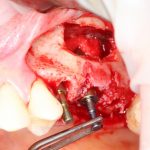

Я зафиксировал костный блок практически без адаптации на несколько винтов. Обрати внимание, что винты находятся в зоне, где не планируется установка имплантатов. Фиксация должна быть надежной, поскольку мне еще предстояла подготовка лунок для имплантатов. Трех винтов для этого вполне достаточно.

Дальнейшая адаптация костного блока свелась к сглаживанию острых краев. После чего я приступил к подготовке лунок и установке имплантатов.

Напомню, что для этой работы я выбрал субкрестальные имплантаты Ankylos C/X. Они прекрасно сочетаются с любым методом остеопластики.

Я не планирую установку супраструктур или коронок, поэтому на уровень первичной стабильности можно положить болт. Даже наоборот — чем меньше крутящий момент при установке, тем лучше. Для имплантатов Ankylos и подобных им, это особенно важно. В общем, момент силы при установке — не более 10-15 Нсм.

Ремарка: имплантаты с предустановленными имплантодержателями хороши тем, что с ними легко контролировать позиционирование имплантатов. В случае с Ankylos С/Х - еще и крутящий момент. Имплантодержатель должен отсоединяться от имплантата с легким щелчком. Если его клинит, и тебе приходится прикладывать для этого усилия, то ты, однозначно, превысил момент силы во время установки имплантата. Следовательно, жди проблем.

Глянем на то, что получилось:

Осталось адаптировать костный блок (убрать острые края), проверить его фиксацию и, при необходимости, добавить винты. Десятисекундное дело.